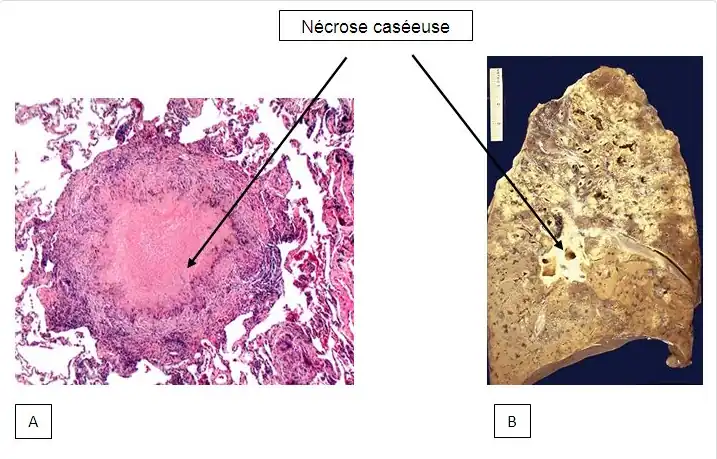

Les cavernes sont une complication fréquente de la tuberculose pulmonaire[54]. On appelle caverne une cavité creusée au sein du parenchyme pulmonaire[55]. Les bacilles tuberculeux se développent initialement dans le poumon sous forme de nodules, appelés granulomes, qui sont peu à peu entourés de lymphocytes et de macrophages destinés à contenir l'infection[54]. Un granulome peut évoluer soit vers la disparition sans cicatrice, soit vers la caverne, sans que les mécanismes sous-jacents soient compris en totalité[55]. Les vestiges de macrophages détruits occupent le centre du granulome et forment la majeure partie de la nécrose caséeuse[55]. Chez certains patients, cette nécrose caséeuse se liquéfie et devient un milieu de culture adapté aux bacilles, qui prolifèrent. Des enzymes protéolytiques érodent alors la capsule fibreuse située en périphérie du granulome, et son centre liquide peut alors se vider peu à peu[55]. Lorsqu'une caverne tuberculeuse arrive en communication avec l'arbre bronchique, la dissémination des bacilles dans l'air expiré augmente la contagiosité[54],[56]. Par ailleurs, la quantité importante de bacilles contenus dans les cavernes favorise le développement de résistances aux anti-tuberculeux[56].

L’examen anatomopathologique se pratique sur l’échantillon résultant de la biopsie. Il met en évidence une lésion spécifique à la tuberculose dite : granulome épitheloide gigantocellulaire à centre caséeux nécrosé. Le terme de granulome désigne l’ensemble des éléments cellulaires présents dans un foyer inflammatoire. Le foyer tuberculeux est entouré d’une grande cellule polynucléaire résultant de la fusion des macrophages tel que mentionné dans la physiopathologie de la maladie[53].